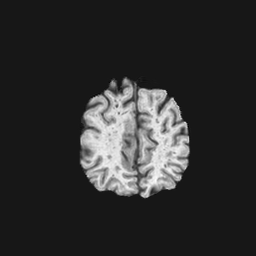

Exp. 1: Segmented adult brain data is used to evaluate our network’s regression performance with known ground truth Tisubscript𝑇𝑖T_{i}. 85 brains from the ADNI data set[1] were randomly selected; 70 brains for ΩtrainsubscriptΩ𝑡𝑟𝑎𝑖𝑛\Omega_{train} and 15 brains for ΩvalidationsubscriptΩ𝑣𝑎𝑙𝑖𝑑𝑎𝑡𝑖𝑜𝑛\Omega_{validation}. Fig. 2 shows an example slice of the ground truth and the reconstructed ΩΩ\Omega.

Figure 2: Example slice from the segmented adult brain MRI data set (a); reconstruction from 300 ωisubscript𝜔𝑖\omega_{i} based on SVRNet regression without SVR (b); SVR initialised with SVRNet predictions after eight iterations of SVR (c). Note that SVRNet (b) predicts individual slice transformations only from image intensities without any initial world co-ordinates of the sampled slice. (d) shows the achieved PSNR in dB when comparing the volumes of (b) and (c) to (a).

Reconstructing from Ti^^subscript𝑇𝑖\hat{T_{i}} initialisation without SVR yields a PSNR of 23.7 ±plus-or-minus\pm 1.09; with subsequent SVR the PSNR increases to 29.5±plus-or-minus\pm2.43 when tested on 15 randomly selected test volumes after four iterations of SVR.